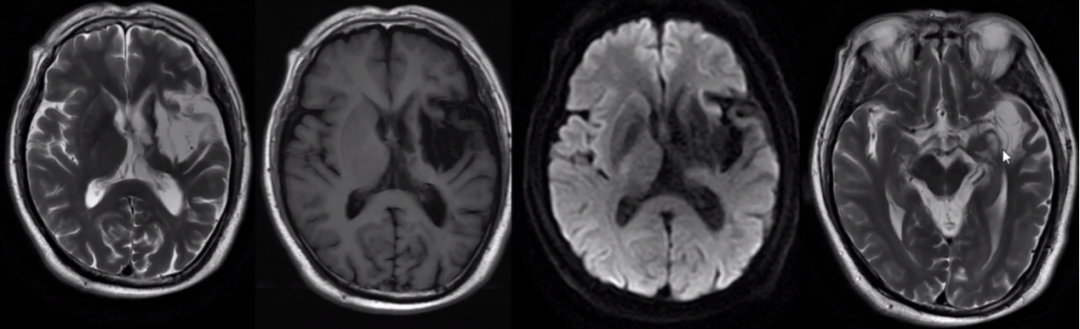

2.脑出血影像学表现

信号特征复杂,与血管内红细胞的完整性及血红蛋白的演变有关。

(1)超急性期 CT 高密度;T1WI 呈等或略低信号,T2WI 呈高信号。

(2)急性期 CT 高密度;T1WI 呈等信号,T2WI 呈低信号。

(3)亚急性期 CT 密度逐渐减低与脑实质相仿 1w、t2 呈高信号。

(4)慢性期 CT 囊性病灶,可见钙化;T2WI 高信号血肿周围被低信号含铁血黄素包饶。